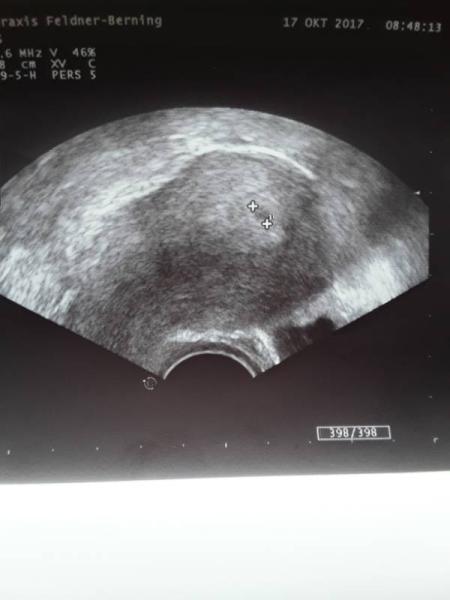

War heute bei meiner Gyn (früher als ich eigentlich wollte) Abstrich war nur minimal auffällig,soll Milchsäure Kapseln einmal die Woche nehmen. US hat sie auch gemacht und was soll ich sagen, man sah eine Fruchthöhle :) wie erwartet noch recht klein und unscheinbar (5,4 mm) aber mehr als beim letzten mal. Sie wollte sich mit der SSW noch nicht festlegen,da mein Zyklus lang war und jegliche ungenaue Angabe würde mich nur verunsichern ( google und so ;) In zehn Tagen soll ich wieder kommen und dann wissen wir hoffentlich mehr

Bild zu Vorsichtige Freude - Schwanger - wer noch? Rund um die Schwangerschaft

Ist bei dir und dem baby alles gut? Wann wurde das Bild gemacht? Habe ein ganz ähnliches Bild bei gerade 5+3...